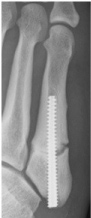

Patient 2: 20-year-male, basketball player

In February 2013, pain around the fifth metatarsal gradually worsened. The patient was diagnosed with a stress fracture of the fifth metatarsal (Figure 3a). However, bone union had not been achieved at 3 months after the original injury, so the patient was treated with one round of ESWT and fracture line became unclear at 4-weeks after the first round of treatment (Figure 3b). And he returned to basketball because of pain relief. However, he got pain around the fifth metatarsal again and refracture occurred at 3 months after ESWT (Figure 3c). The patient received surgery, screw fixation. However, bone union had not been achieved at 11-weeks after the refracture (Figure 3d). And then he was treated with two rounds of ESWT again over a period of 4-weeks and bone union was achieved at 9-weeks after the first round of re-ESWT (Figure 3e). He returned to competition at 12-weeks after ESWT.

Figure 3D: X-ray of non union at 11weeks after surgery in Patient 2. View Figure 3D

Figure 3E: X-ray of at 9 weeks after re-ESWT in Patient 2. View Figure 3E